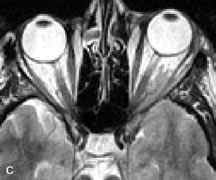

On MRI, uveal melanomas have a typical appearance that helps to differentiate them from other primary and secondary intraocular tumors as well as choroidal detachments. Pigmented melanomas are hyperintense on Tl-weighted images, hypointense on T2-weighted studies, and hyperintense on proton density–weighted examinations (Fig. 24).30,31,50,80–82 These signal characteristics have been attributed to the paramagnetic properties of melanin because of stable free radicals that shorten the T1 and T2 relaxation times. Moderate enhancement is seen on postgadolinium T2-weighted images. Gadolinium-enhanced T1-weighted images are particularly sensitive in detecting choroidal melanomas.83 MRI may be less sensitive in detecting extrascleral extension of tumor than echography performed by an experienced ultrasonographer.84

Fig. 24. A. T1- and (B) T2-weighted MR scans demonstrate a small nodular intraocular mass (arrows) that is very hyperintense on the T1-weighted scan and hypointense on the T2-weighted image. This signal intensity pattern is due to the presence of free radicals within melanin granules. C and D. Postcontrast fat-suppressed T1-weighted scans demonstrate homogeneous intense enhancement of the lesion and no evidence of seleral penetration or optic nerve invasion.